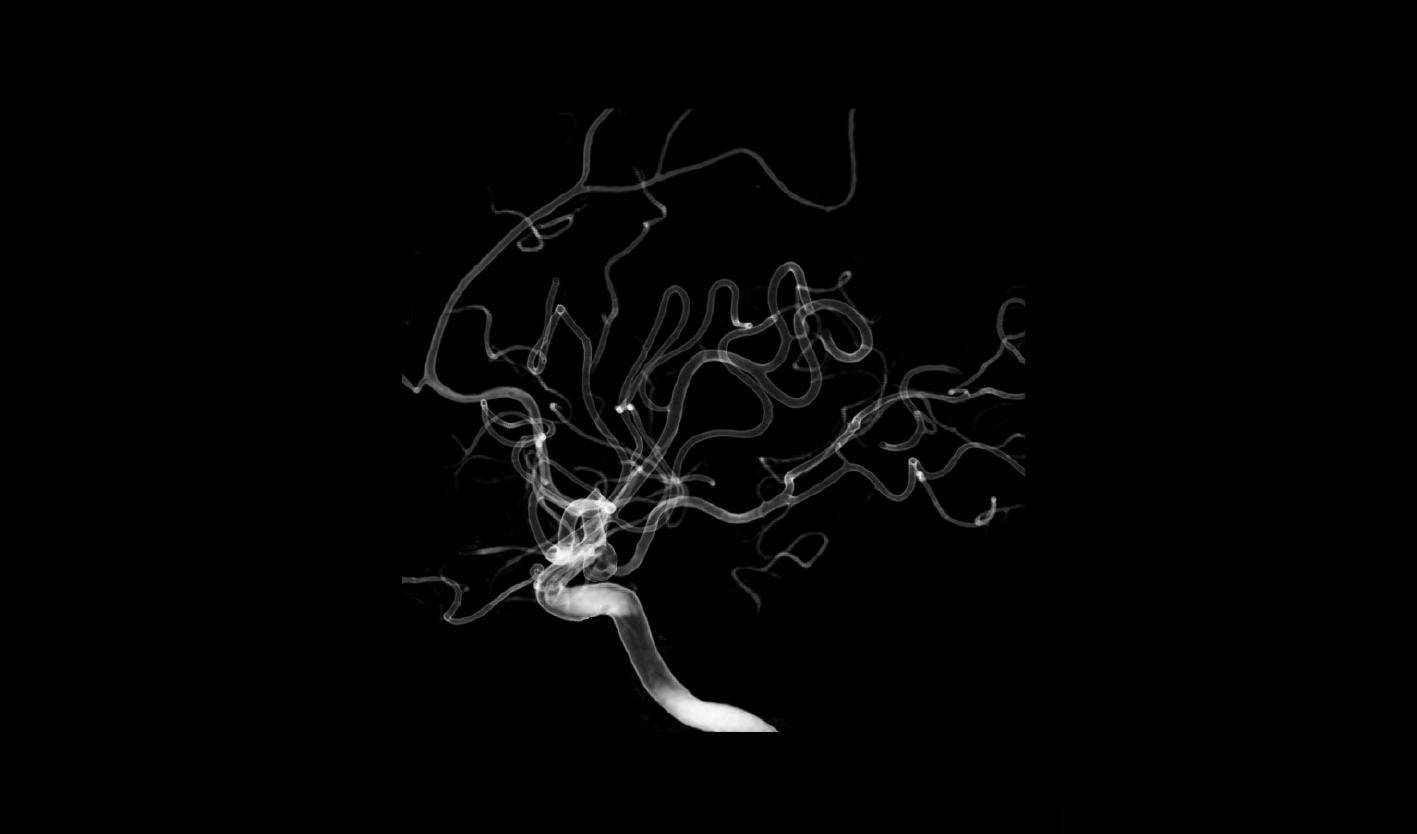

精微小血管可视

2K超清影像链,精至微小血管一览无余